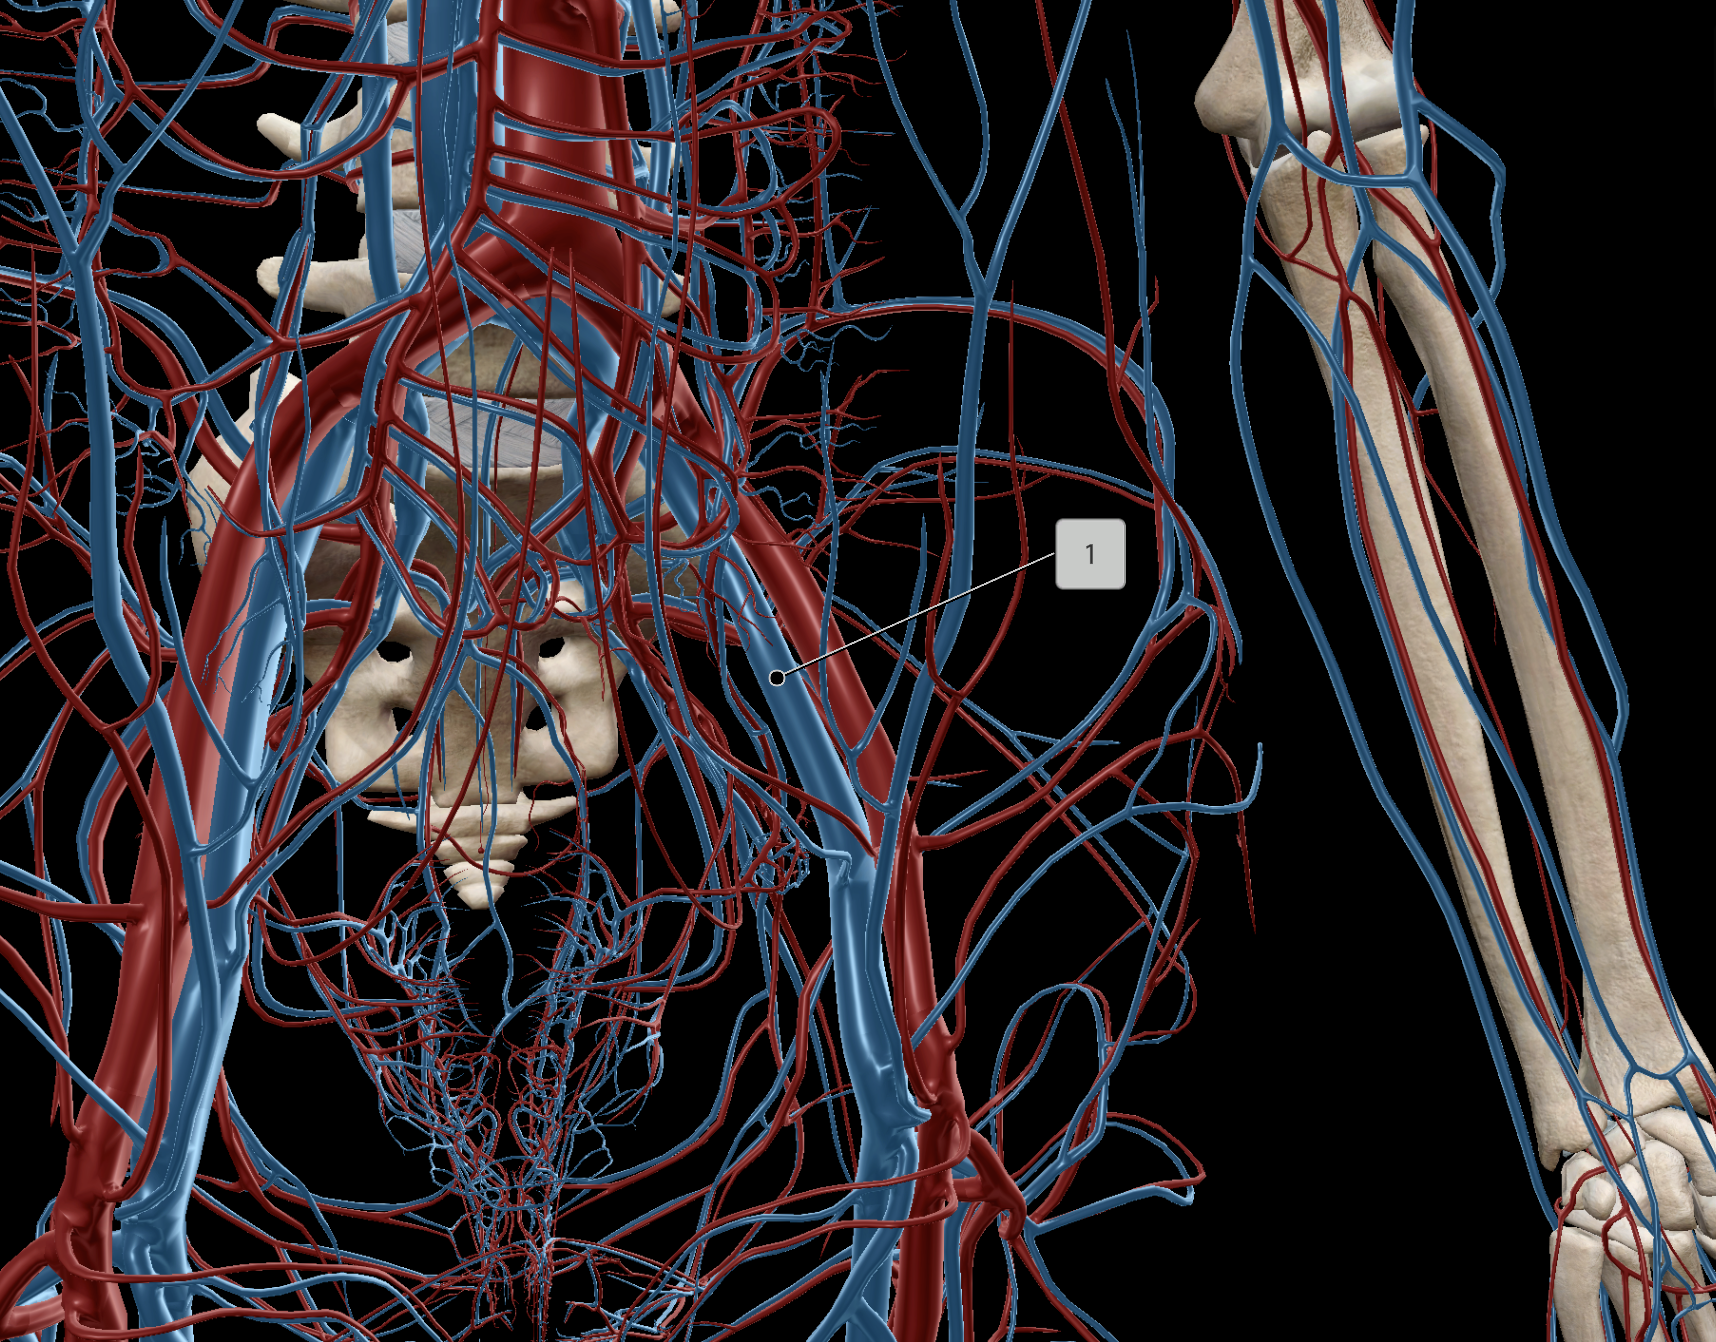

Common Iliac Artery

Internal Iliac Artery

External Iliac Artery

Femoral Vein

Common Iliac Vein

External Iliac Vein

Internal Iliac Vein